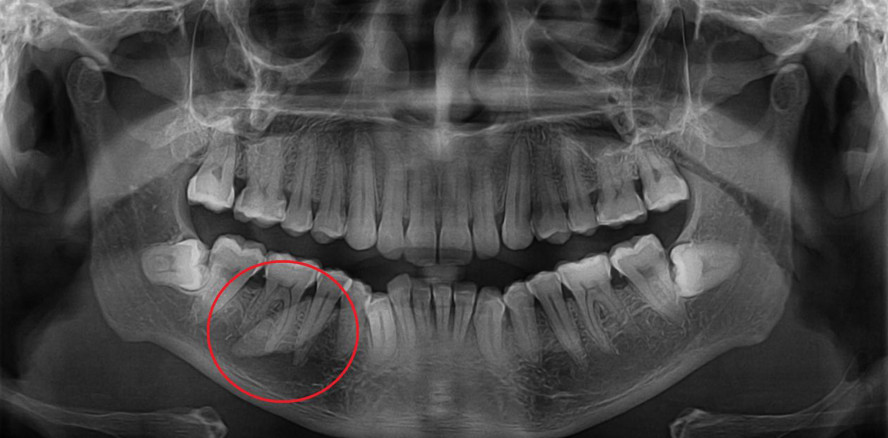

Ein männlicher Patient wurde an die Oralchirurgie mit dem Vorhaben, einen retinierten Zahn zu extrahieren, verwiesen. Doch wie sich herausstellte, handelte es sich dabei gar nicht um einen Zahn, sondern einen Sialolithen.

So auch im Fall des 37-jährigen indischen Patienten, der über starke Schmerzen im rechten Unterkiefer klagte. Akut wurden sie jedoch immer in Verbindung mit Kaubewegungen. Darüber hinaus war das Vermögen der Mundöffnung des Patienten stark eingeschränkt – auf lediglich 15 Millimeter.

Anhand einer Sonografie ließ sich der Übeltäter jedoch schnell ermitteln: Ein gut zwei Zentimeter großer Sialolith. Unter Vollnarkose wurde dem Inder der Speichelstein chirurgisch entfernt.